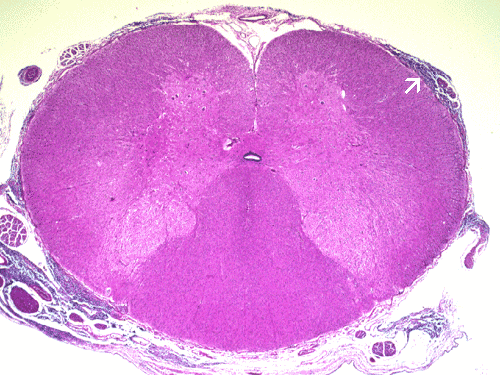

- Panel C: Medulloblastoma has a high tendendy to

disseminate throught the brain and spinal cord. The tumor cells are

illustrated by the arrow. Therefore, treatment for medulloblastoma usually

includes irradiation of the entire brain and spinal cord.